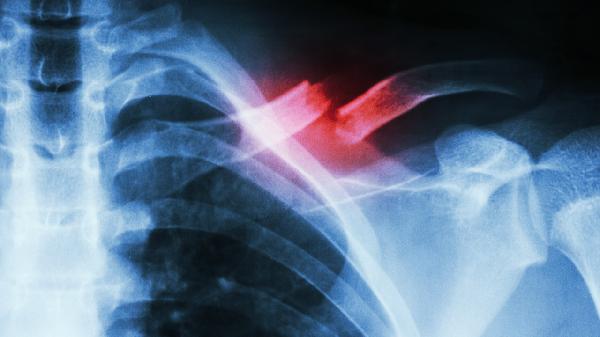

乳腺癌、肺癌、胃癌等恶性肿瘤可能通过淋巴道转移至锁骨下淋巴结。转移性淋巴结通常质地坚硬、活动度差、增长迅速且无压痛。左侧锁骨上淋巴结肿大需警惕胃癌转移可能。确诊需依靠淋巴结活检病理检查,治疗需针对原发肿瘤采取手术、放疗或化疗等综合措施。